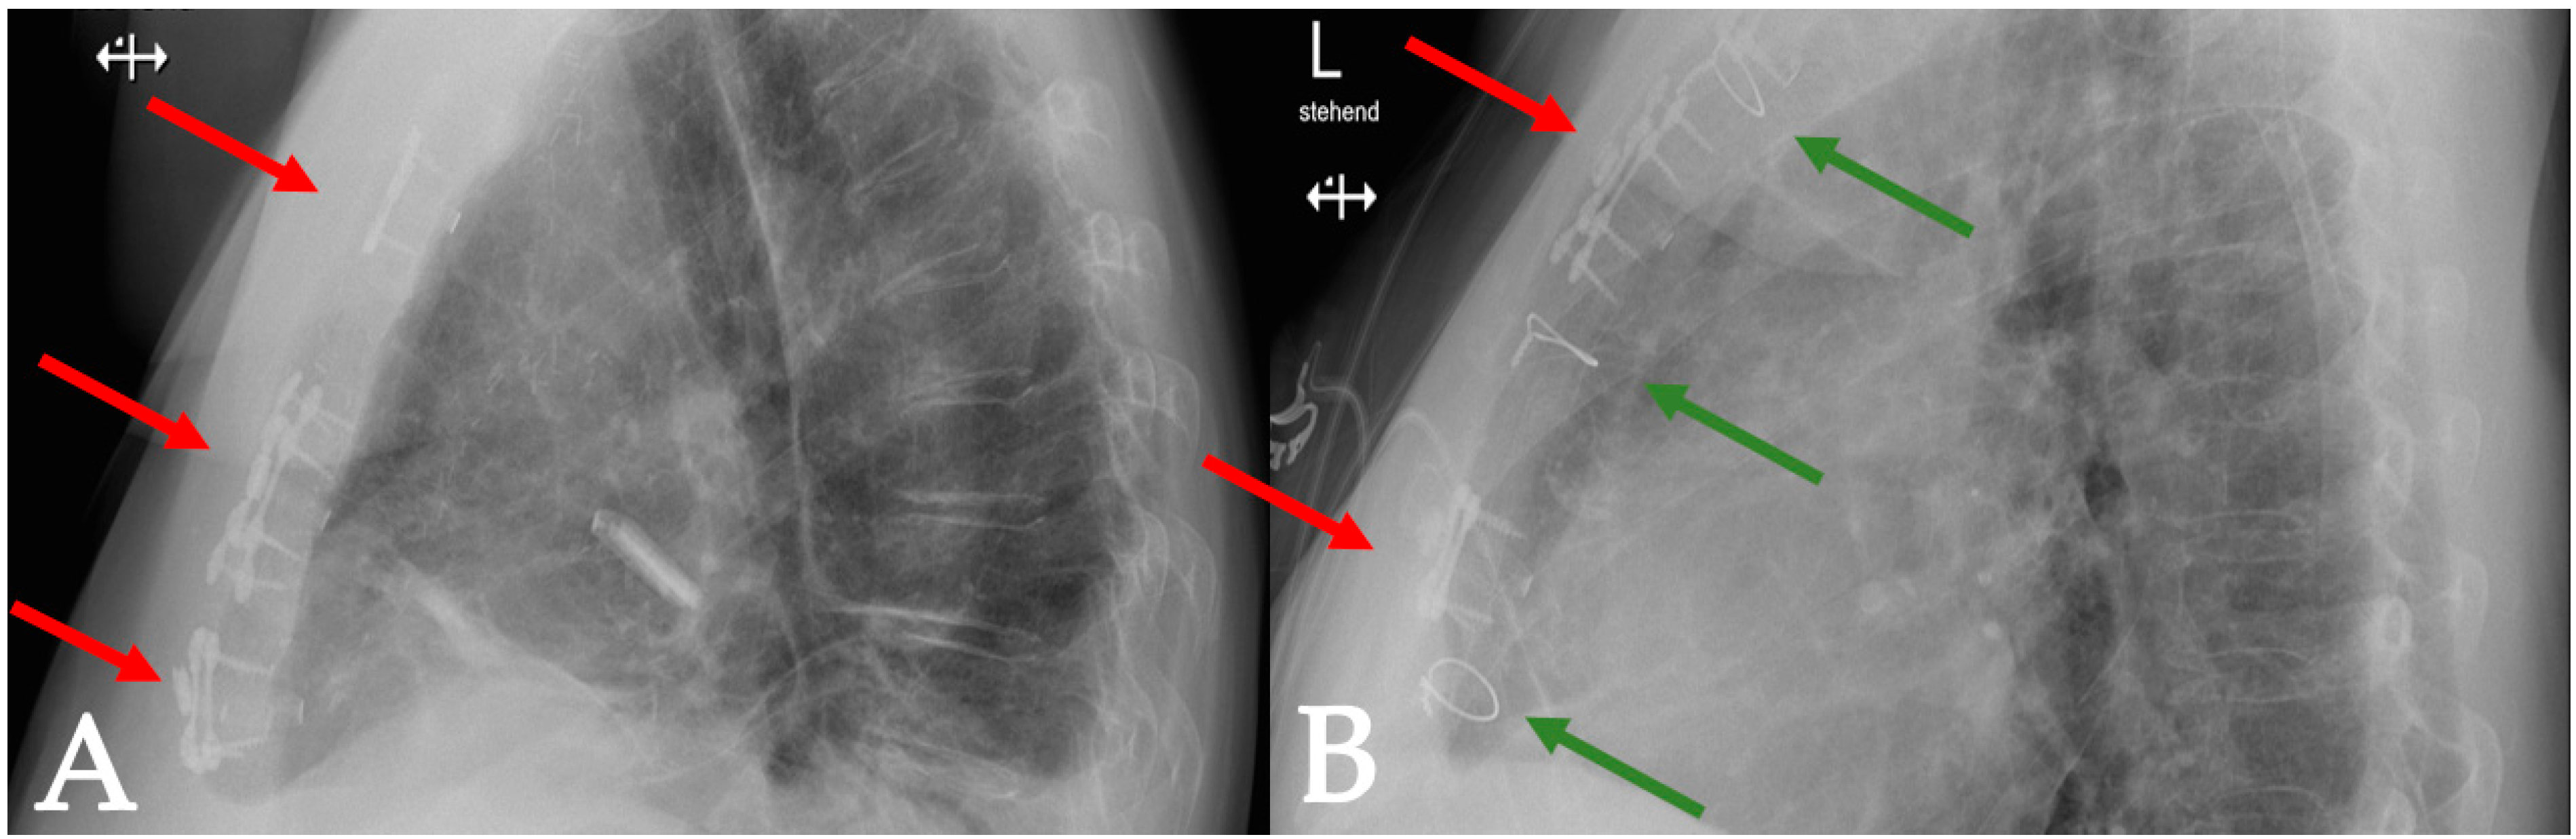

4.1.1. Case 1

4.1.2. Case 2